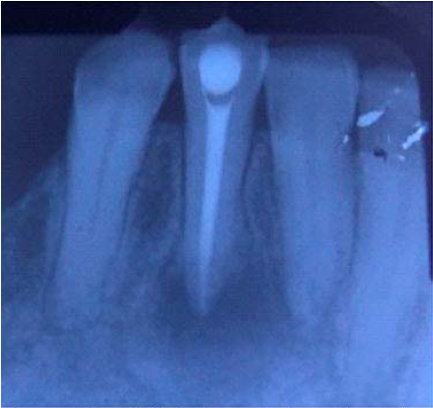

Paciente femenina y 49 años de edad que acude a la clínica de endodoncia de la Universidad de Cartagena refiriendo necesitar tratamiento de conducto en diente antero inferior derecho. No refiere sintomatología dolorosa y responde negativamente a las pruebas de sensibilidad, la radiografía periapical revela zona radiolucida a nivel apical de aproximadamente 9mm de diámetro, así mismo se aprecia ápice en pico de flauta compatible con reabsorción apical de los últimos 3mm del mismo. Clínicamente se observa atrición dental y vestibularización de dicho diente, así como leve cambio de color de la corona. Se realiza el diagnóstico de Periodontitis Apical Asintomática y se planifica el tratamiento de endodoncia con preparación invertida que se inicia en la misma cita.

Se realizó instrumentación del sistema de conductos hasta longitud de trabajo y se colocó hidróxido de calcio como medicación intracanal, se programa una próxima cita a los 7 días después, no obstante la paciente acude 48 horas después refiriendo dolor severo alrededor de 24 horas posteriores a la intervención, al examen clínico se aprecia inflamación y perdida de contorno gingival a nivel dientes anteroinferiores derechos (Figura 1).

Por tal motivo se retoma el tratamiento previa anestesia e irrigación con hipoclorito de sodio y se formula a la paciente analgésicos y antibióticos, así como una inyección intramuscular de 4mg de dexametasona, una vez controlado el dolor se programa nueva cita en 5 días; en esta se anestesia nuevamente, se realiza aislamiento absoluto, no se aprecia contenido purulento dentro del conducto por lo cual se procede a instrumentar hasta longitud de trabajo, al no encontrarse tope apical, se decide colocar Mineral Trióxido Agregado (MTA) para crear tapón apical en los últimos 4mm de la raíz y posteriormente se obtura el resto del conducto con gutapercha en otra cita y el diente es restaurado (Figura 2).